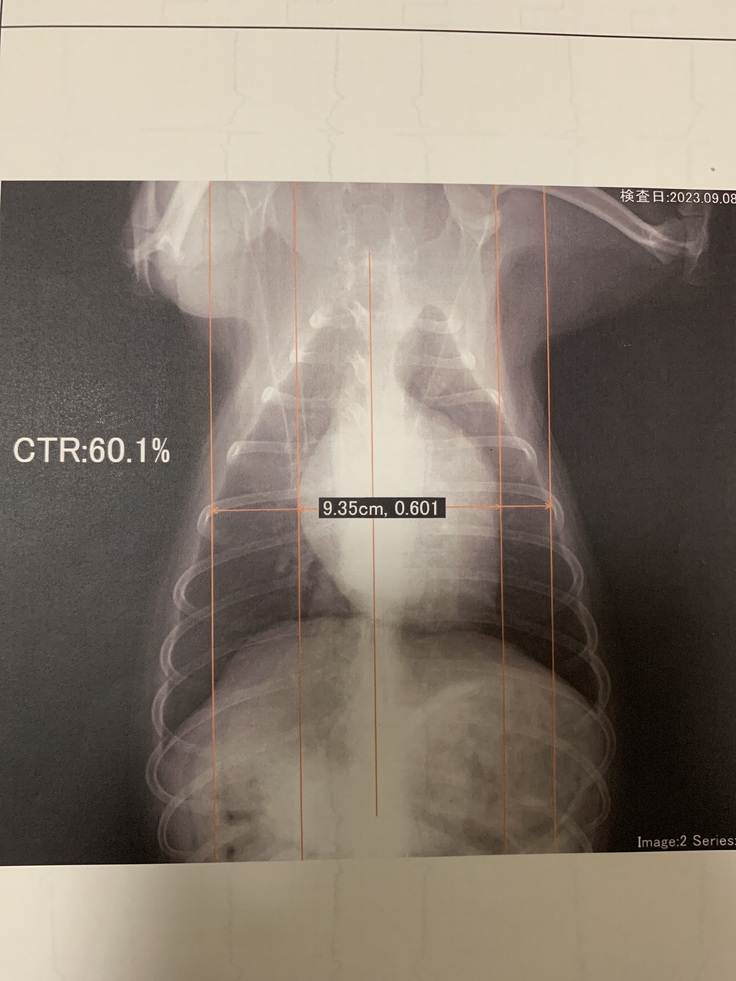

※レントゲン写真

レントゲン写真では、心臓が肥大しており、クラスb2の(心不全発症)直前レベルである事も分かりました。 心臓から送りだす血液には逆流が見られ

重度のレベルであり、

やはり手術しないと治らないと判断されました。